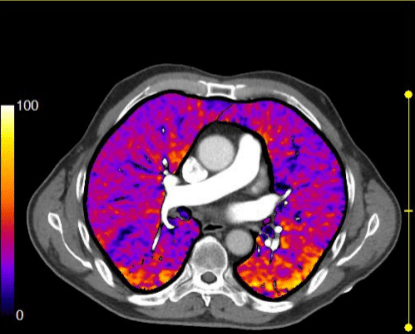

Na tomografia de tórax, com uso de contraste, são analisadas as estruturas vasculares da região estudada. A solução de contraste iodado é administrada por via endovenosa e distribui o contraste entre as estruturas com fluxos sanguíneos, realçando as estruturas hipervascularizadas, mostrando, por exemplo, tumores ou processos inflamatórios.